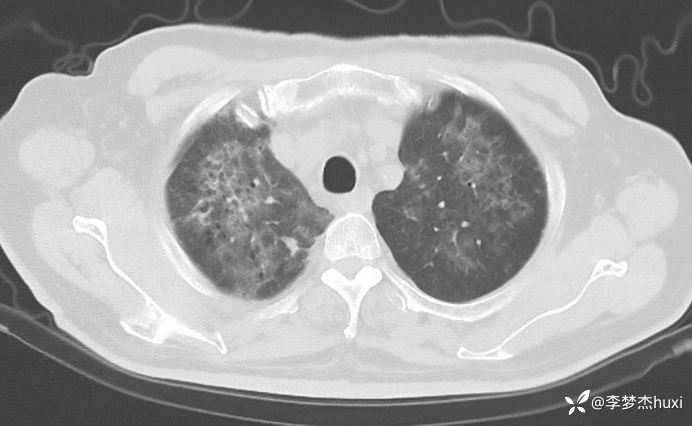

男性74岁,莫西沙星治疗加重的肺炎,可能什么病原菌?

既往史:既往高血压病史 20 余年,最高 180/90mmHg,平素口服降压零号治疗,控制可;糖尿病病史 20 余年,平素应用诺和灵 30R,控制良好;右肺鳞癌病史11月,放疗结束3天,期间放射性食管炎,目前仍吞咽痛;否认冠心病病史;否认“肝炎”、“结核”等传染病史;否认外伤史,否认手术史,无输血史,否认药物、食物过敏史;预防接种史不详,系统回顾无特殊。。

治疗经过:莫西沙星、喜炎平治疗进展

讨论:可能什么病原体?